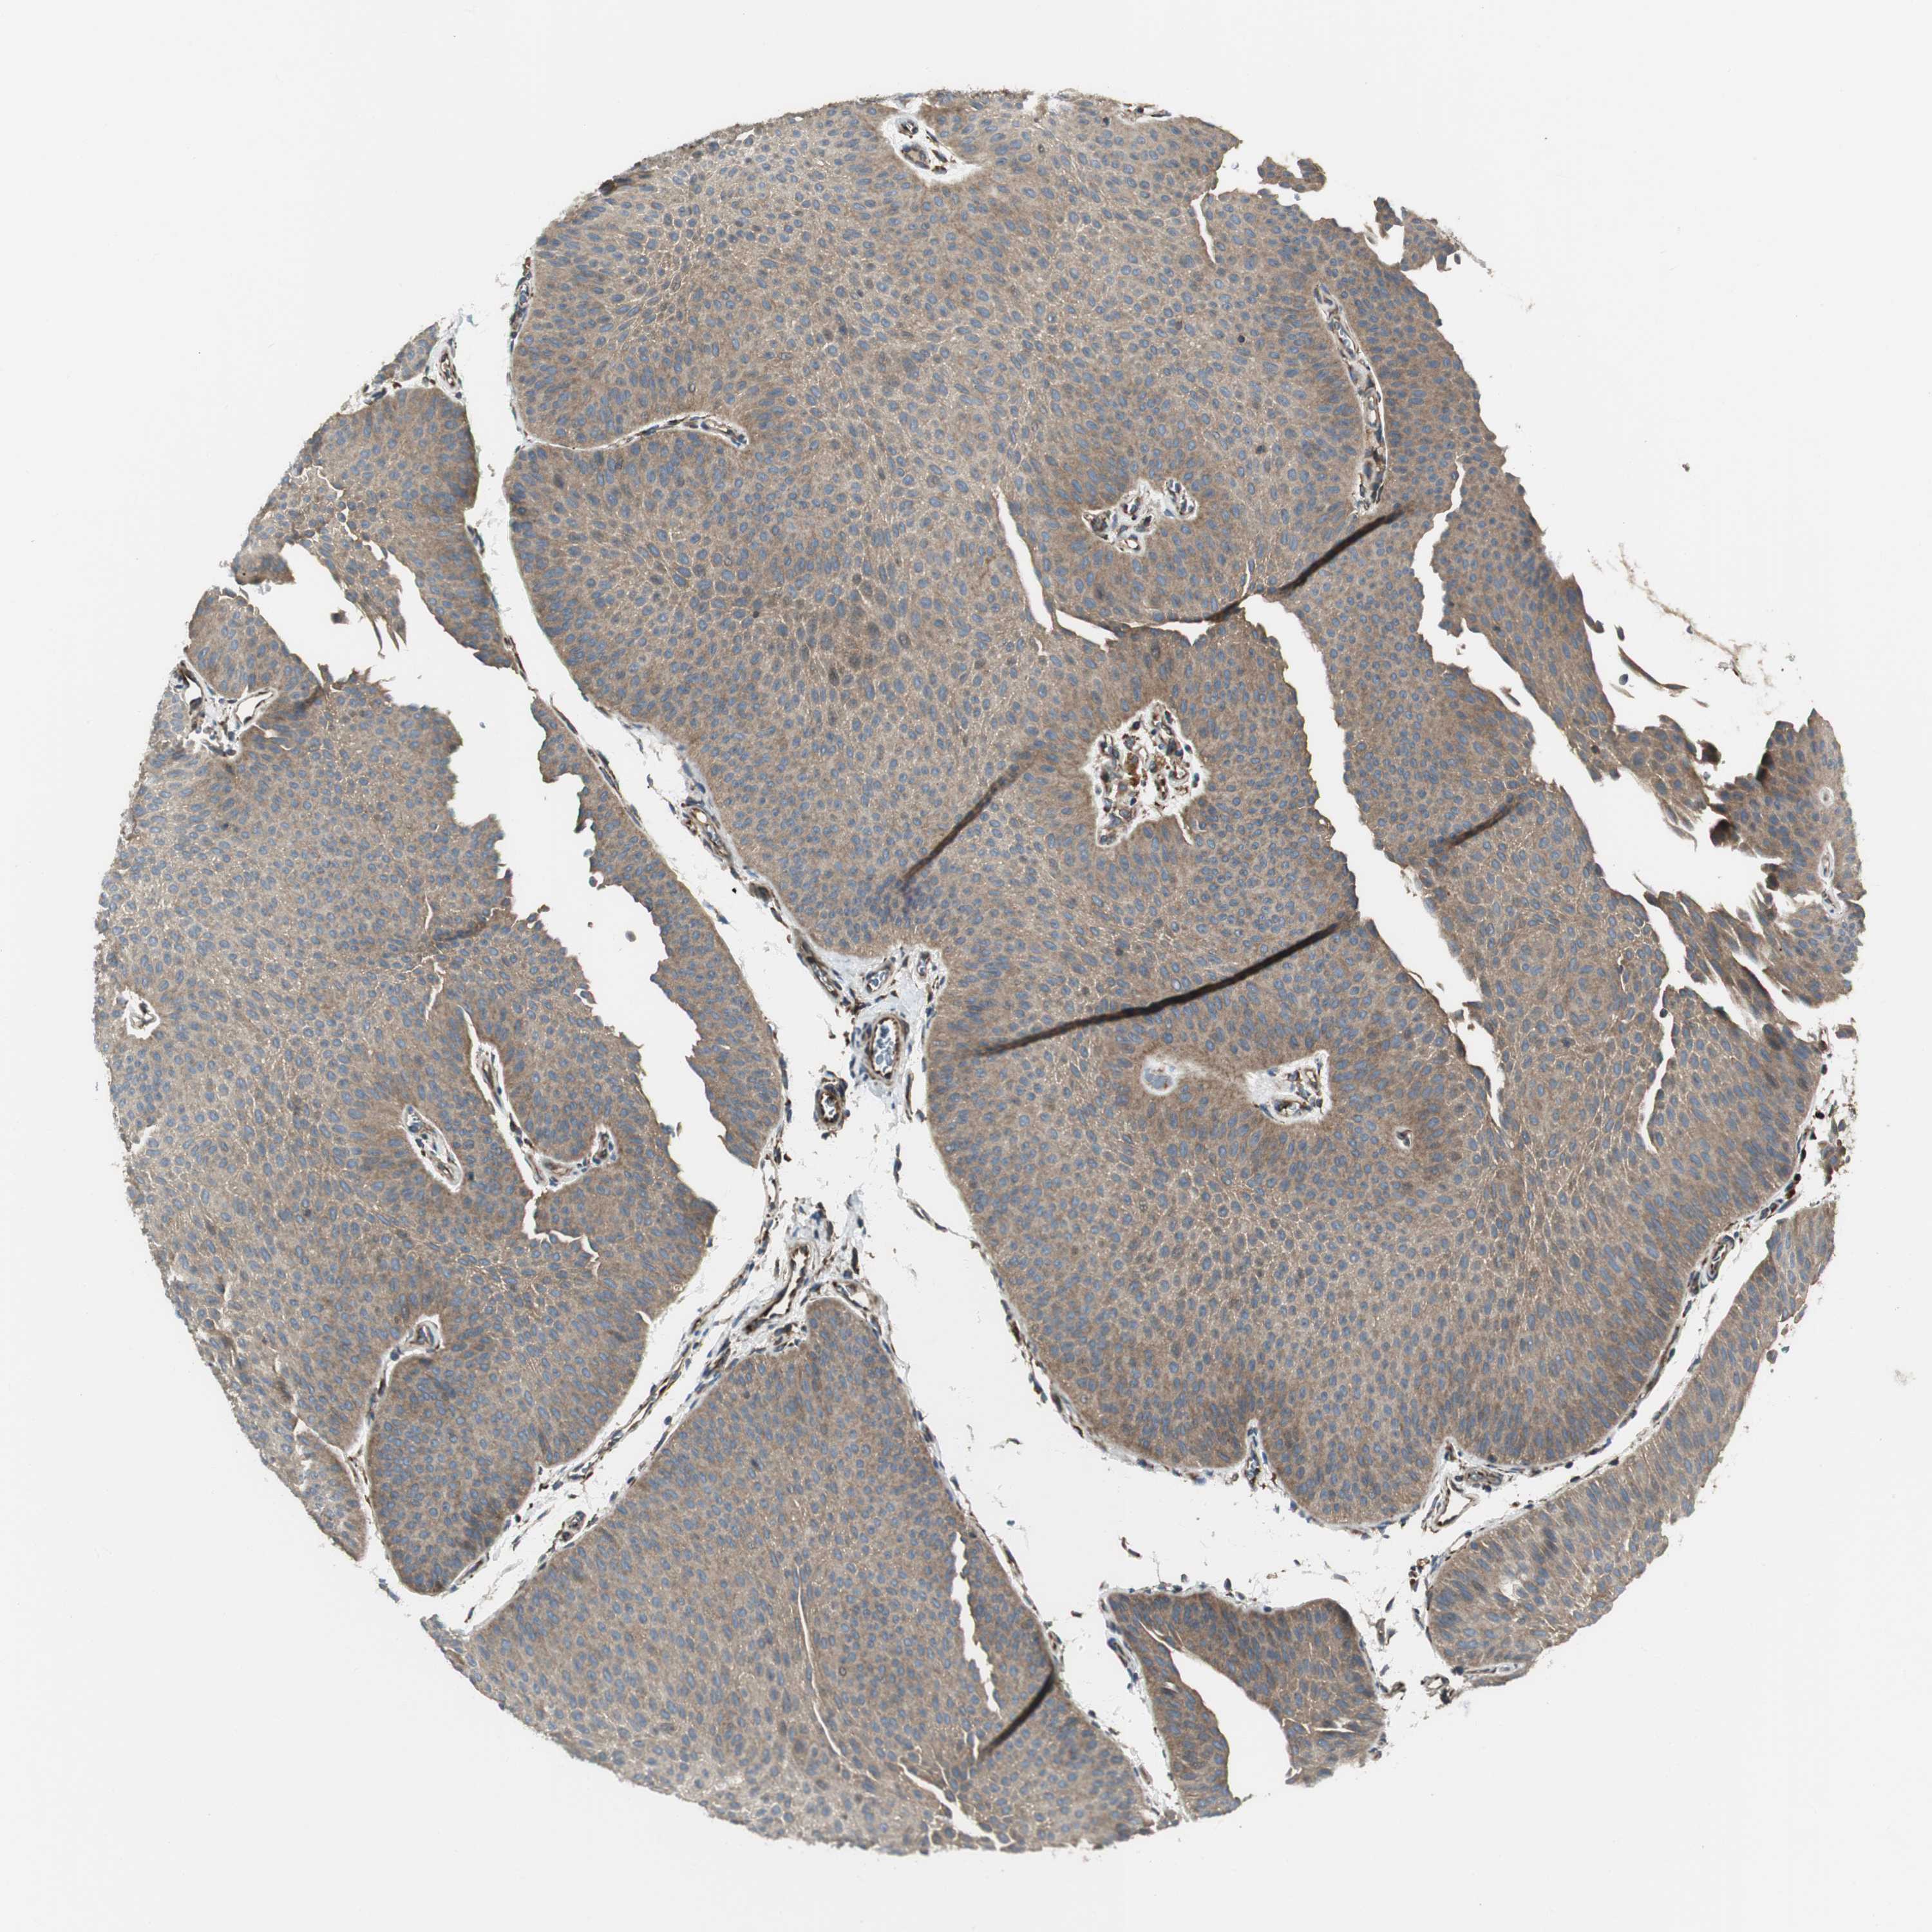

UROTHELIAL CANCER - Protein expressioni

A mouse-over function shows sample information and annotation data. Click on an image to view it in a full screen mode. Samples can be filtered based on level of antibody staining by selecting one or several of the following categories: high, medium, low and not detected. The assay and annotation is described here.

Note that samples used for immunohistochemistry by the Human Protein Atlas do not correspond to samples in the TCGA dataset.

Antibody stainingi

Antibody staining in the annotated cell types in the current human tissue is reported as not detected, low, medium, or high, based on conventional immunohistochemistry profiling in selected tissues. This score is based on the combination of the staining intensity and fraction of stained cells.

Each image is clickable and will lead to virtual microscopy that enables deeper exploration of all samples and also displays staining intensity scores, fraction scores and subcellular localization as well as patient and tissue information for each sample.

Antibody HPA007699

Antibody CAB009629

Urothelial carcinoma, Low grade